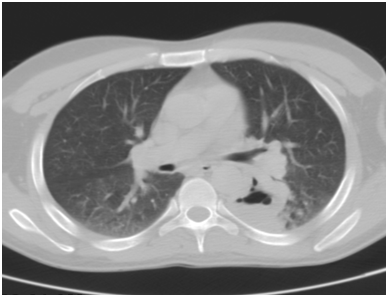

After about a week there was no improvement in the patient’s condition. By this time, the c-ANCA was reported as positive. Hence, a diagnosis of Wegener’s granulomatosis was made. He was then transferred to the internists’ care. Although the patient was out of our care but for the sake of interest rest of his clinical course is described from this point. Soon, he developed acute renal failure and in a matter of five days, his urea increased from 4.9mmol/L to 51mmol/L and serum creatinine to 1200umol/L. There was significant proteinuria of 6g/dl. He required hemodialysis for about two weeks and also a few sessions of plasmapheresis. His renal biopsy was done that showed crescentic glomerulonephritis (Figure 3). The nasal biopsies were sent for second opinion and also demonstrated vasculitis (Figure 4). He was put on pulsed intravenous cyclophosmamide 0.4mg/m2 and oral prednisolone 80mg OD followed by oral cyclophosmamide 100mg OD and prednisolone 60mg OD. Soon the general condition of the patient improved and his renal profile also became normal. He was then managed on out-patient basis on maintenance therapy of cyclophosmamide and prednisolone in varying doses ranging from 50-100mg OD and 20-40mg OD respectively depending upon the disease activity. For example, he had ‘flares’ of the disease in the form of left exudative pleural effusion that needed multiple tapping. It finally resolved. Then, he had left pneumothorax that was encysted (Figures 5 & 6) and it resolved on its own. Currently, 7-years on, the patient is in clinical remission and follows every month with us for decrusting of nose due to severe atrophic rhinitis.

Figure 3 Renal biopsy showing crescetic glomerulonephritis.